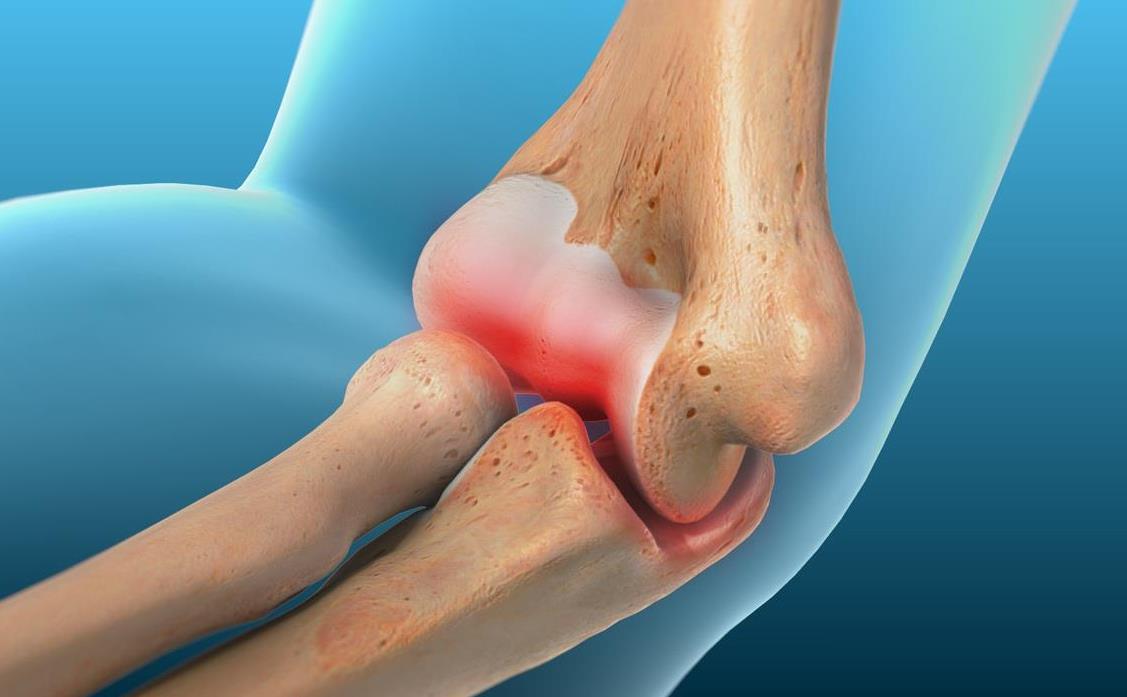

Traumas graves o accidentes, fracturas o

LESIONES

Las lesiones en las manos suelen producirse por un accidente inesperado o por un uso continuado a lo largo del tiempo. Independientemente de la razón, el dolor de una lesión en la mano puede resultar desconcertante en su vida diaria.

El Dr. Fernando Romero se especializa en el tratamiento de lesiones de la mano, la muñeca, el antebrazo y el codo.